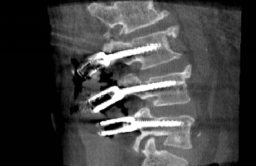

高刚性机械臂和高速磨钻的结合降低了骨面打滑的几率,保证了快速而精准的置钉操作。术后O-arm扫描显示椎板磨削范围与规划保持一致,两例共12枚椎弓根螺钉均实现快速精准置入(图5)。

图5 O-arm术后扫描验证螺钉位置近年来,脊柱外科机器人发展迅速,临床应用价值与社会经济效益不断得到证实,但目前所有此类型的机器人技术均为单纯轴向定位,即术者仅能在机械臂的引导下实施以骨道钻孔等为主的外科操作,而无法实施椎板等骨结构的磨削,大大限制了其在椎管减压等手术的临床应用。本次手术所使用的新一代多功能脊柱外科机器人系统是由中国医科大学附属第一医院骨科、北京天智航医疗科技股份有限公司天玑实验室与重庆西山科技股份有限公司共同合作研发,其基于力与光学追踪的“主动约束”交互控制策略,使医生轻松实现在“约束体积”下柔顺和高效的人机协同磨削操作。高速磨钻是脊柱外科最为常用的高效动力工具,但徒手操作需要一定经验,磨削深度和边界不易控制,机器人的高精度和磨钻的高效率相结合,使精准和高效连续磨削成为可能。磨削减压和置钉一体化手术机器人成功应用于临床,拓展了脊柱外科手术机器人的功能,达到了国际领先水平。